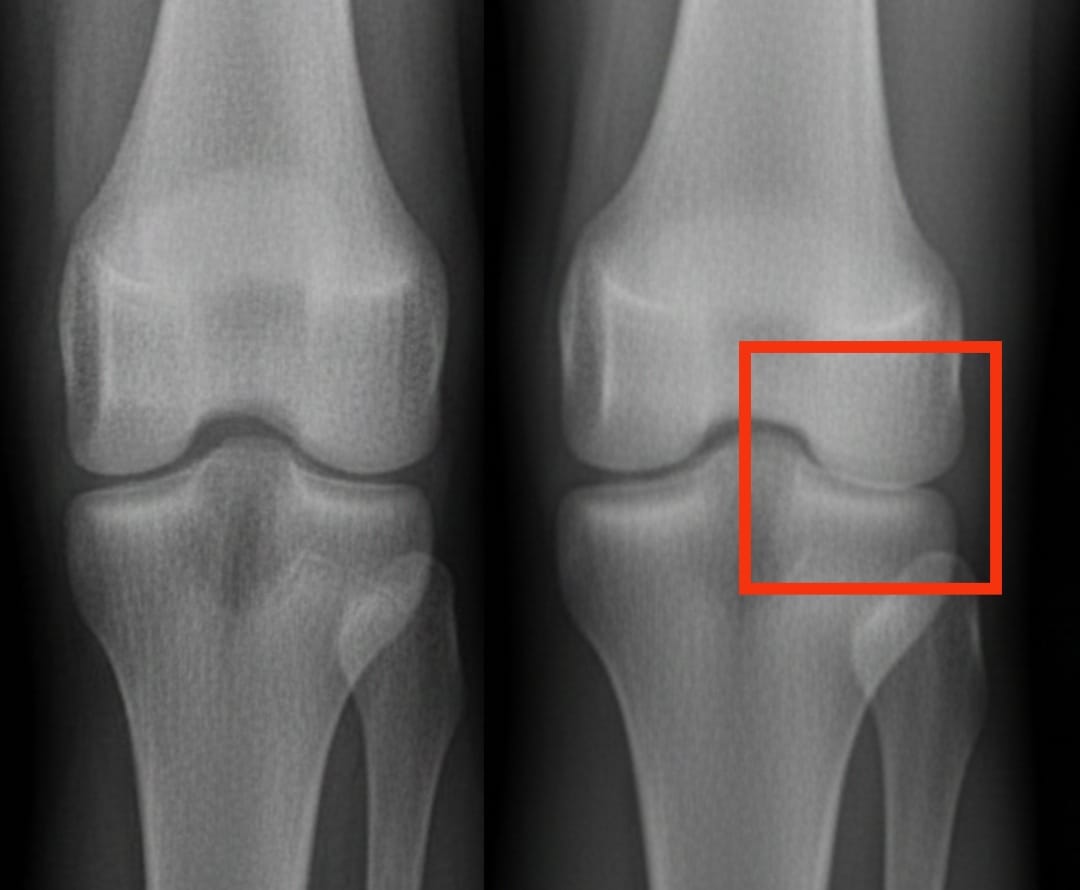

血小板濃縮血漿治療膝關節炎比其他注射療法更有效嗎?

膝關節炎影響著全球數億人。其特徵是軟骨逐漸磨損,導致疼痛和活動困難。在眾多治療方案中,血小板濃縮血漿注射越來越受到關注。這種療法利用患者自身的血液,濃縮其中的血小板,以刺激組織修復並減輕發炎。